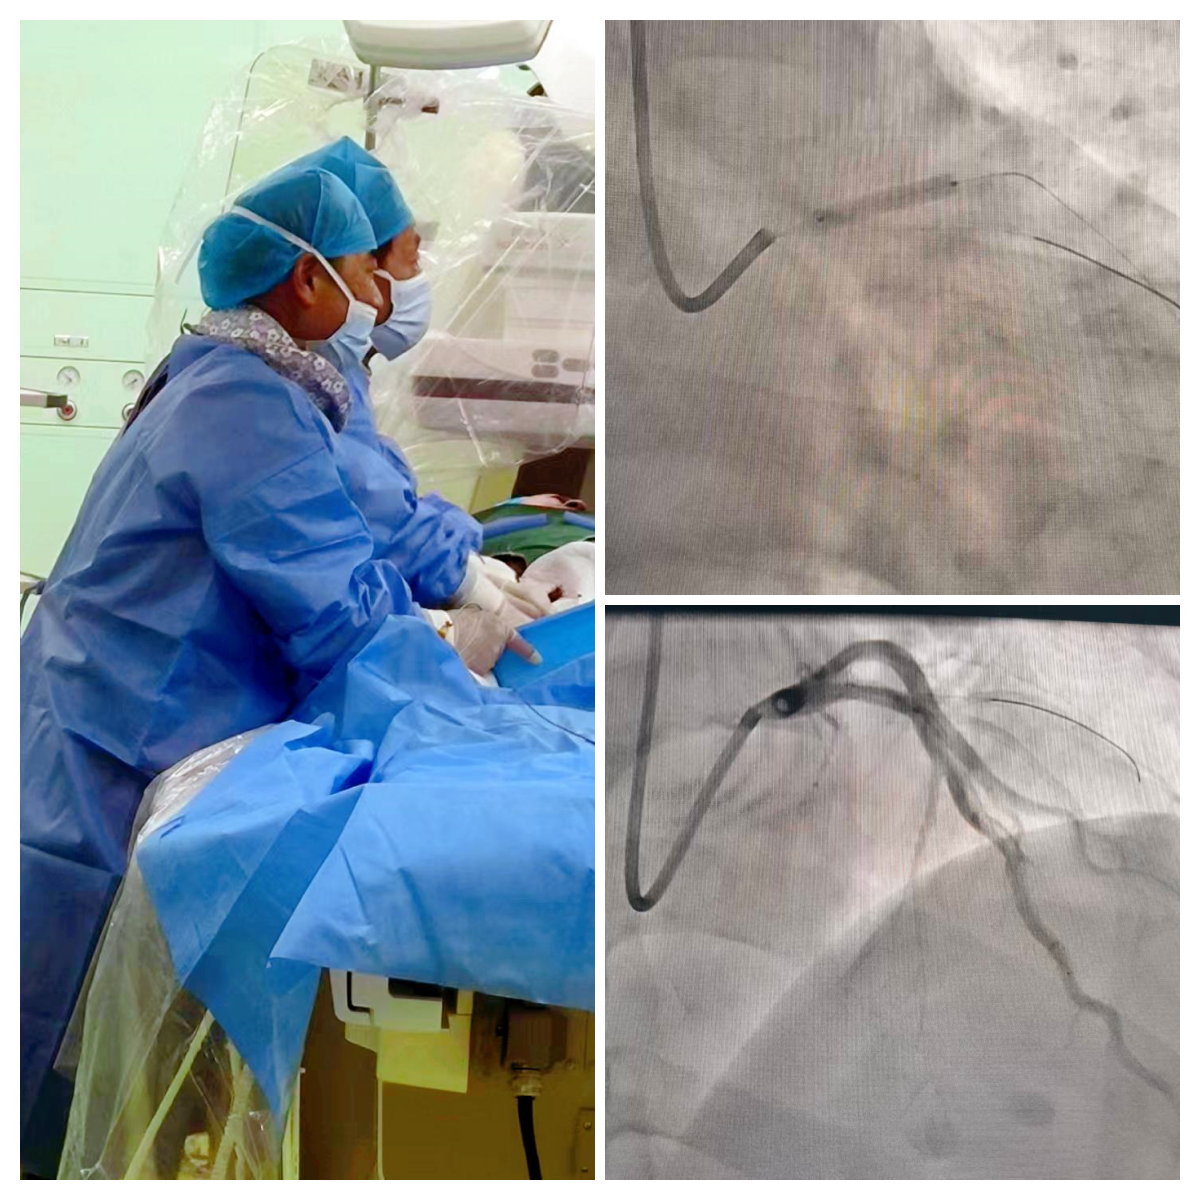

时间就是生命!我院立即启动急性心肌梗塞绿色通道,心血管内科崔松教授团队与导管室护理团队及技师团队无缝对接,同步完成术前准备,紧急开展冠状动脉造影检查。造影结果显示,患者左主干远段及前降支近段血管接近完全闭塞,血流中断,正是导致急性心肌梗塞的核心病因。面对复杂紧急病情,心血管内科介入团队沉着应对,精准操作导管至病变血管处,先行球囊扩张开通闭塞血管,恢复心肌供血,随后成功植入一枚3.5mm*18mm支架,解除血管狭窄问题。整个手术过程紧张有序、精准高效。